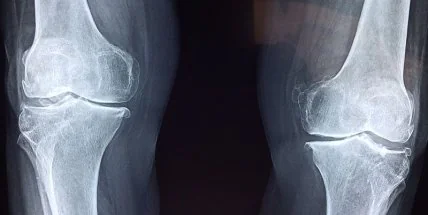

Находясь между костями, хрящи выдерживают вес и смягчают ударную нагрузку на суставы. Но сделать искусственные хрящи в лаборатории очень сложно. Ученые из Университета Дьюка создали экспериментальный гель, который соответствует долговечности и прочности настоящего хряща.

Хрящ - соединительная ткань, достаточно прочная, чтобы выдерживать вес человека и трение от каждого шага, но при этом мягкая, эластичная и облегчает урон от ударов. К сожалению, хрящ может изнашиваться со временем или порваться от травм и очень плохо восстанавливается. До сих пор похожий на него материал было трудно воспроизвести в лабораторных условиях: любые альтернативы не справлялись с нагрузкой.

Для замены хрящей с 1970-х используют гидрогель - он достаточно скользкий, хорошо приживается и не наносит вреда соседним клеткам. Но для несущих суставов, как колено, он слишком слабый, поэтому, если у человека начинаются проблемы с коленом, его приходится менять целиком. Ученые из Университета Дьюка считают, что, наконец, разработали гидрогель, который может сравниться по свойствам с хрящевой тканью. Исследование опубликовано в журнале Advanced Functional Materials.

Станет лекарством: ученые нашли алкоголю новое применениеРазработка может помочь людям, у которых есть проблемы с коленным суставом и которые не хотят по каким-либо причинам соглашаться на его замену (это сложная операция, требующая длительного восстановления, а очереди на нее можно ждать годами). Руководители исследования Бен Уайли и Кен Галл считают, что однажды они предложат альтернативу 600 тысячам операций, выполняемых в США каждый год. Клиническое использование нового гидрогеля начнется в лучшем случае через несколько лет, до этого придется пройти тесты на его безопасность. Тем временем химики планируют создать имплантат, который можно будет протестировать на овцах.